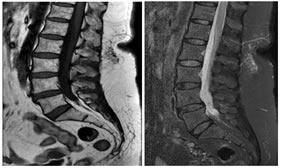

CASE 3

T2 W AXIAL IMAGE AT L3-4 LEVEL SHOWING REDUCED THECAL SAC AREA BUT THERE IS NO COMPRESSION SUGGESTIVE OF PROMINENT EPIDURAL FAT PAD. THERE IS ALSO EVIDENCE OF LIGAMENTUM FLAVUM HYPERTROPHY AND FACETAL ARTHROPATHY

POST CONTRAST T1W CORONAL IMAGE SHOWING ENHANCEMENT OF L3 AND L4 VERTEBRAL BODIES ALONG WITH L3-L4 INTERVERTEBRAL DISC ENHANCEMENT AND PARAVERTEBRAL SOFT TISSUE ENHANCEMENT ON THE LEFT SUGGESTIVE OF SPONDYLODISCITIS.

POST CONTRAST T1W AXIAL IMAGE SHOWING ENHANCEMENT OF PARAVERTEBRAL AND PARASPINAL REGION ON THE LEFT AT THE LEVEL OF L4 VERTEBRAL BODY